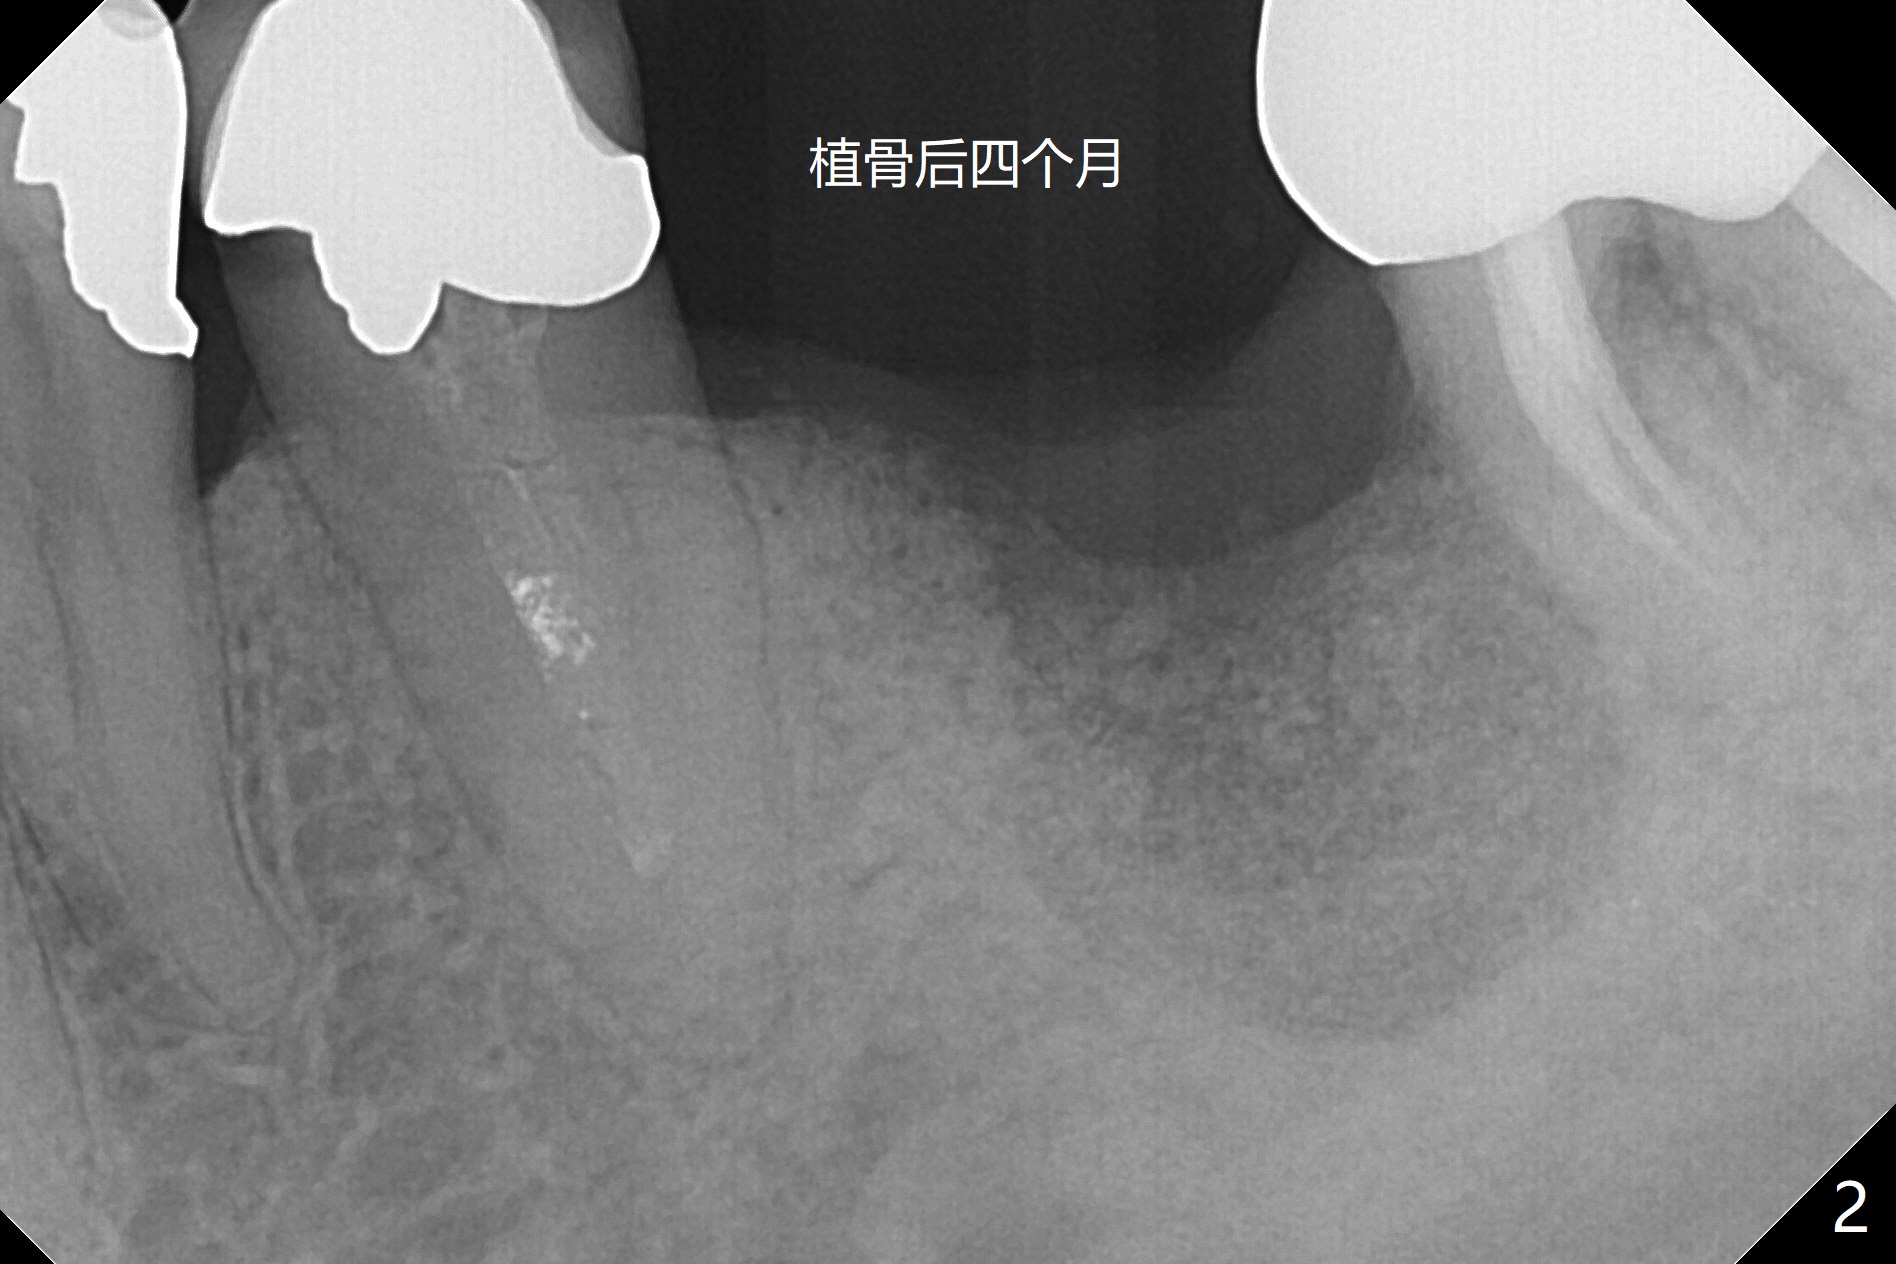

能植牙吗?